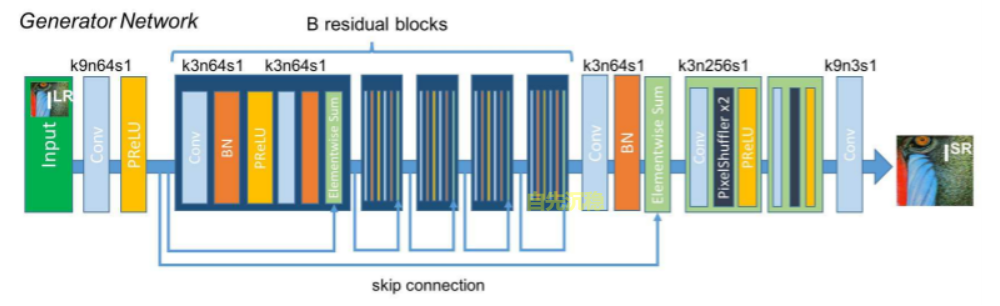

return out10.4、SRResNet

In [35]

from paddle.nn import Layer

from paddle import nn

import math

# 是可以保持w,h不变的

class ConvolutionalBlock(nn.Layer):

"""

卷积模块,由卷积层, BN归一化层, 激活层构成.

"""

def __init__(self, in_channels, out_channels, kernel_size, stride=1, batch_norm=False, activation=None):

"""

:参数 in_channels: 输入通道数

:参数 out_channels: 输出通道数

:参数 kernel_size: 核大小

:参数 stride: 步长

:参数 batch_norm: 是否包含BN层

:参数 activation: 激活层类型; 如果没有则为None

"""

super(ConvolutionalBlock, self).__init__()

if activation is not None:

activation = activation.lower()

assert activation in {'prelu', 'leakyrelu', 'tanh'}

# 层列表

layers = list()

# 1个卷积层

layers.append(

nn.Conv2D(in_channels=in_channels, out_channels=out_channels, kernel_size=kernel_size, stride=stride,

padding=kernel_size // 2))

# 1个BN归一化层

if batch_norm is True:

layers.append(nn.BatchNorm2D(num_features=out_channels))

# 1个激活层

if activation == 'prelu':

layers.append(nn.PReLU())

elif activation == 'leakyrelu':

layers.append(nn.LeakyReLU(0.2))

elif activation == 'tanh':

layers.append(nn.Tanh())

# 合并层

self.conv_block = nn.Sequential(*layers)

def forward(self, input):

output = self.conv_block(input)

return output

# w,h放大

class SubPixelConvolutionalBlock(nn.Layer):

def __init__(self, kernel_size=3, n_channels=64, scaling_factor=2):

super(SubPixelConvolutionalBlock, self).__init__()

# 首先通过卷积将通道数扩展为 scaling factor^2 倍

self.conv = nn.Conv2D(in_channels=n_channels, out_channels=n_channels * (scaling_factor ** 2),

kernel_size=kernel_size, padding=kernel_size // 2)

# 进行像素清洗,合并相关通道数据 放大了图像

self.pixel_shuffle = nn.PixelShuffle(upscale_factor=scaling_factor)

# 最后添加激活层

self.prelu = nn.PReLU()

def forward(self, input):

output = self.conv(input)

output = self.pixel_shuffle(output)

output = self.prelu(output)

return output

class ResidualBlock(nn.Layer):

"""

残差模块, 包含两个卷积模块和一个跳连.

"""

def __init__(self, kernel_size=3, n_channels=64):

"""

:参数 kernel_size: 核大小

:参数 n_channels: 输入和输出通道数(由于是ResNet网络,需要做跳连,因此输入和输出通道数是一致的)

"""

super(ResidualBlock, self).__init__()

self.conv_block1 = ConvolutionalBlock(in_channels=n_channels, out_channels=n_channels, kernel_size=kernel_size,

batch_norm=True, activation='PReLu')

# 第二个卷积块

self.conv_block2 = ConvolutionalBlock(in_channels=n_channels, out_channels=n_channels, kernel_size=kernel_size,

batch_norm=True, activation=None)

def forward(self, input):

"""

前向传播.

:参数 input: 输入图像集,张量表示,大小为 (N, n_channels, w, h)

:返回: 输出图像集,张量表示,大小为 (N, n_channels, w, h)

"""

residual = input # (N, n_channels, w, h)

output = self.conv_block1(input) # (N, n_channels, w, h)

output = self.conv_block2(output) # (N, n_channels, w, h)

output = output + residual # (N, n_channels, w, h)

return output

class SRResNet(nn.Layer):

# SRResNet(scaling_factor=2)

def __init__(self, large_kernel_size=9, small_kernel_size=3, n_channels=64, n_blocks=16, scaling_factor=2):

"""

:参数 large_kernel_size: 第一层卷积和最后一层卷积核大小

:参数 small_kernel_size: 中间层卷积核大小

:参数 n_channels: 中间层通道数

:参数 n_blocks: 残差模块数

:参数 scaling_factor: 放大比例

"""

super(SRResNet, self).__init__()

# 放大比例必须为 2、 4 或 8

scaling_factor = int(scaling_factor)

assert scaling_factor in {2, 4, 8}, "放大比例必须为 2、 4 或 8!"

# 第一个卷积块

self.conv_block1 = ConvolutionalBlock(in_channels=1, out_channels=n_channels, kernel_size=large_kernel_size,

batch_norm=False, activation='PReLu')

# 一系列残差模块, 每个残差模块包含一个跳连接

self.residual_blocks = nn.Sequential(

*[ResidualBlock(kernel_size=small_kernel_size, n_channels=n_channels) for i in range(n_blocks)])

# 第二个卷积块

self.conv_block2 = ConvolutionalBlock(in_channels=n_channels, out_channels=n_channels,

kernel_size=small_kernel_size,

batch_norm=True, activation=None)

# 放大通过子像素卷积模块实现, 每个模块放大两倍 log2 2=1

n_subpixel_convolution_blocks = int(math.log2(scaling_factor))

self.subpixel_convolutional_blocks = nn.Sequential(

*[SubPixelConvolutionalBlock(kernel_size=small_kernel_size, n_channels=n_channels, scaling_factor=2) for i

in range(n_subpixel_convolution_blocks)])

# 最后一个卷积模块

self.conv_block3 = ConvolutionalBlock(in_channels=n_channels, out_channels=1, kernel_size=large_kernel_size,

batch_norm=False, activation='Tanh')

def forward(self, lr_imgs):

"""

:参数 lr_imgs: 低分辨率输入图像集, 张量表示,大小为 (N, 3, w, h)

:返回: 高分辨率输出图像集, 张量表示, 大小为 (N, 3, w * scaling factor, h * scaling factor)

"""

output = self.conv_block1(lr_imgs) # (16, 3, 24, 24)

residual = output # (16, 64, 24, 24)

output = self.residual_blocks(output) # (16, 64, 24, 24)

output = self.conv_block2(output) # (16, 64, 24, 24)

output = output + residual # (16, 64, 24, 24)

output = self.subpixel_convolutional_blocks(output) # (16, 64, 24 * 2, 24 * 2)

sr_imgs = self.conv_block3(output) # (16, 3, 24 * 2, 24 * 2)

return sr_imgs

if __name__ == '__main__':

img_channel = 1

width = 64

net = SRResNet()

inp = P.randn((1, 1, 120, 120),dtype='float32')

out = net(inp)

print('inp',inp.shape)

print('out',out.shape)inp [1, 1, 120, 120] out [1, 1, 240, 240]